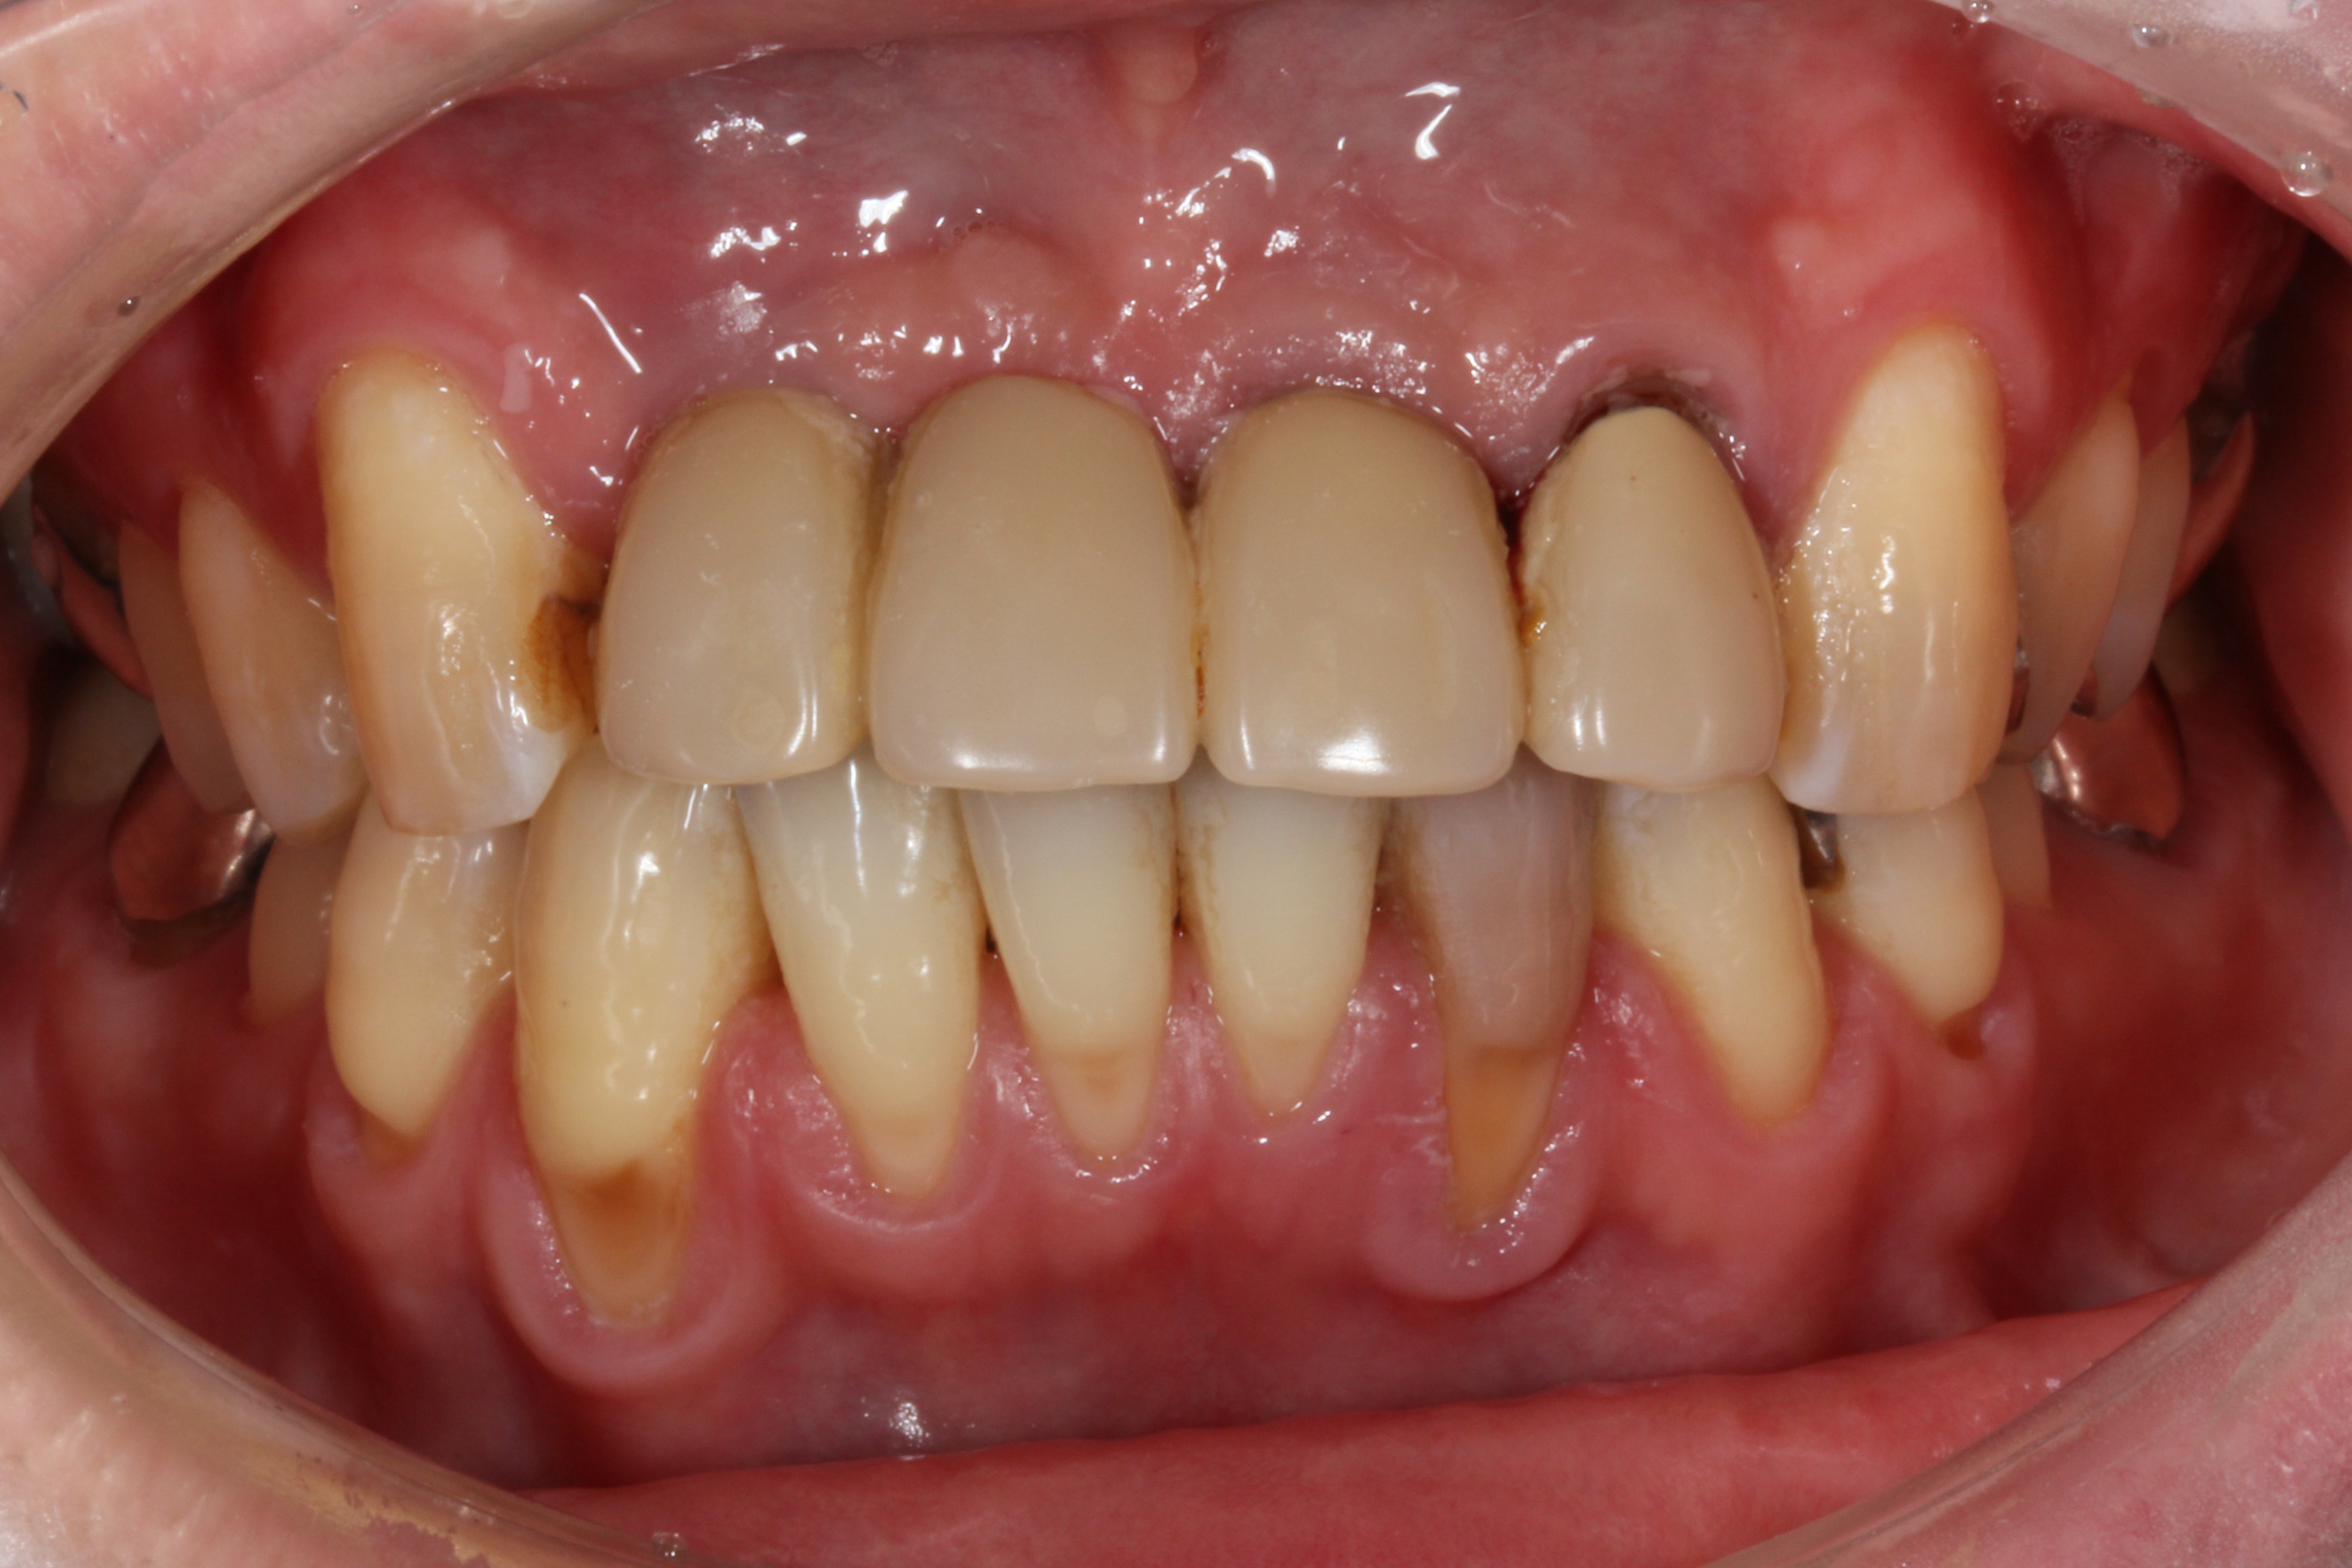

初診時

他医院で根管治療をした前歯 (左上1番2番、右上2番)に根尖病巣が再発し、ブリッジが動揺(ぐらぐら)して噛めないというお悩みでご来院されました。見た目では解りませんが、レントゲンを撮影すると根尖病巣が進行して上顎の骨吸収(骨が溶ける)まで進行している状態でした。

一見すると歯ぐきが腫れている程度に見えますが、実際は動揺も大きく柔らかい食べものでも難儀するような状況でした。レントゲン写真でも根管治療をした3本の歯(1本は抜歯済)の周りに骨が無いことがわかります。